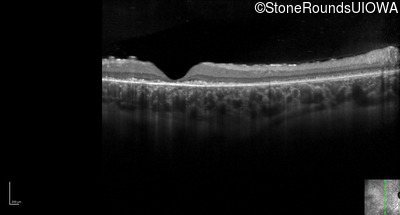

Optical Coherence Tomography - Right - 20/125 +1 sc

Exemplar / OCT Stack

Optical Coherence Tomography - Left - 20/125 -1 sc